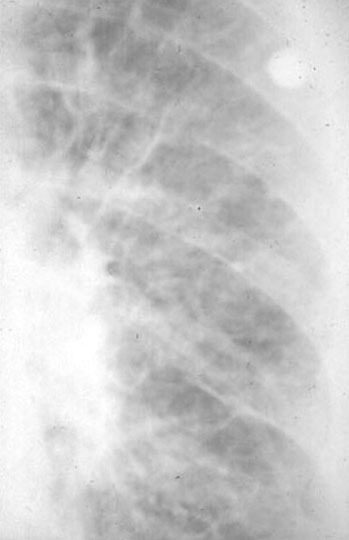

CXR